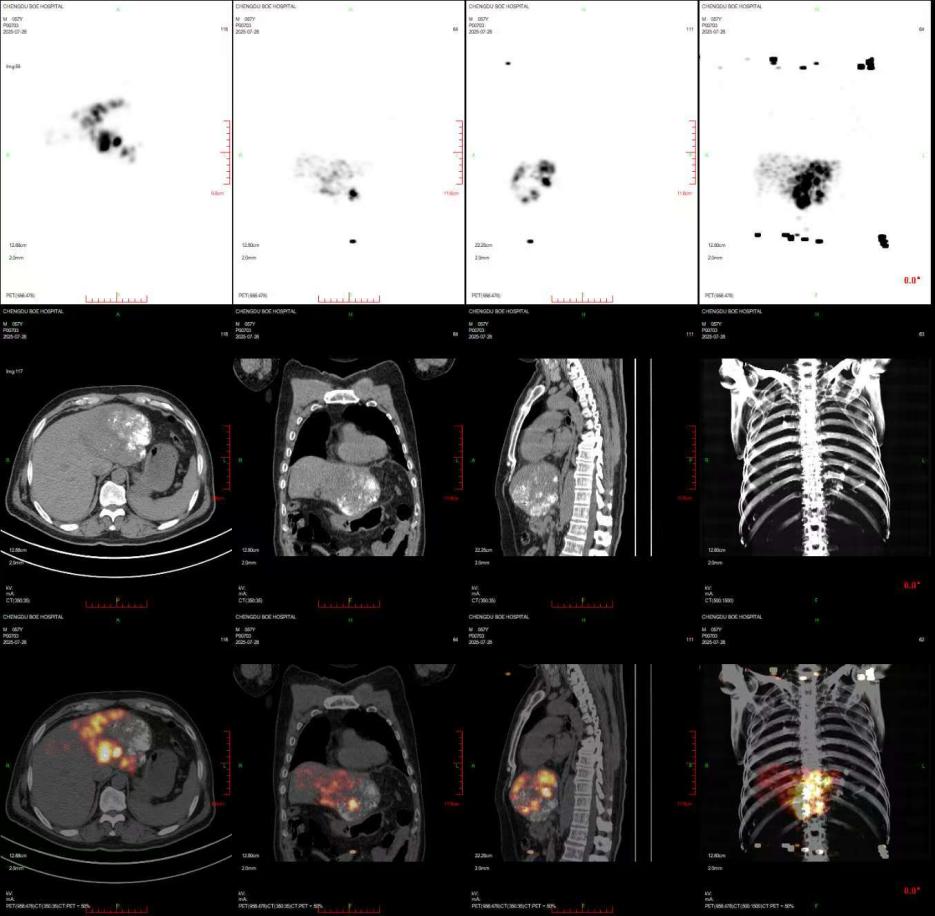

术后,经核医学科 PET-CT 检查验证为冉先生注入的钇 90 树脂微球充分进入到预定病灶,与术前的模拟评估一致,表明钇 90 树脂微球沉积于肿瘤的效果达到预期,目前冉先生已顺利出院。